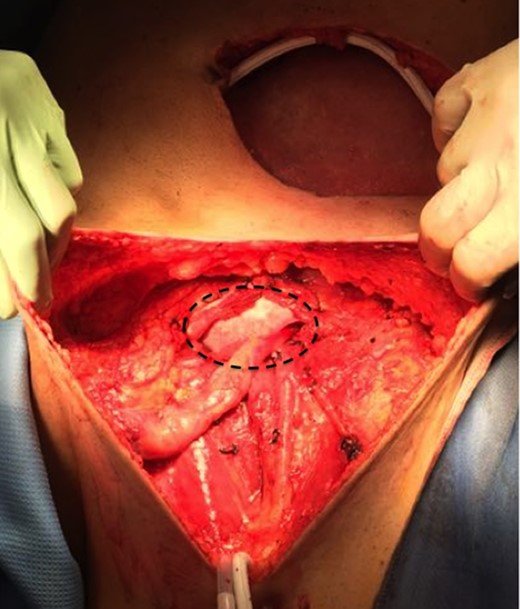

Then a right mastectomy with third level axillary lymphadenectomy, for sentinel lymph node positivity; removal of the left abdominal mass with resection of the band of external oblique muscle and of the infiltrated anterior inguinal wall; lymphadenectomy of the external and common left iliac artery; deep and superficial left inguinal lymphadenectomy (Fig. 2) were performed. Reconstruction of the abdominal band and of the inguinal canal wall was obtained using a GORE® BIO-A® prosthesis (Fig. 3).

Inguinal region after linfoadenectomy (N, nerve; V, Vein; A, Artery; *spermatic cord).